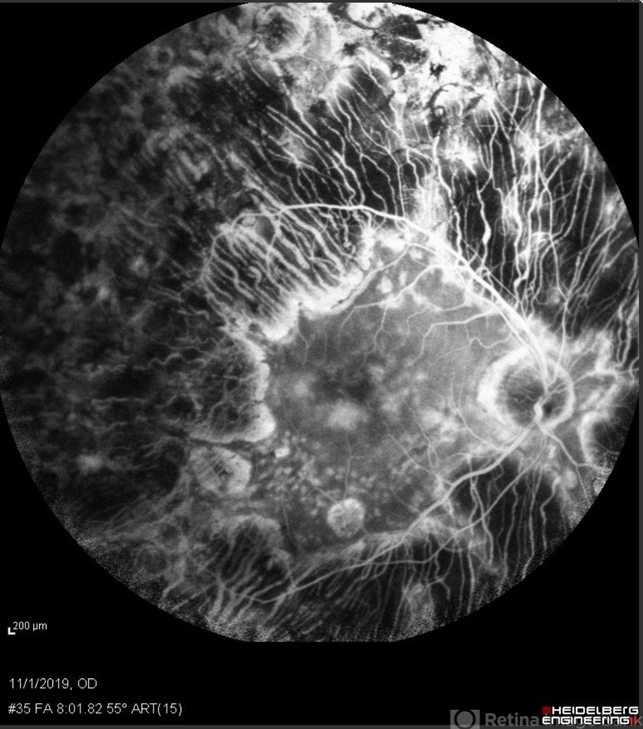

- proliferative diabetic retinopathy (PDR), laser photocoagulation, laser injury

- Scanning laser ophthalmoscope

- Fluorescein angiogram from a 71-year-old woman who underwent numerous sessions of pan retinal laser photocoagulation for proliferative diabetic retinopathy in the remote past. Note the widespread severe secondary atrophy, with only the central macular RPE remaining. Note the choroidal vessels through the diffuse window defect in the peripheral macula and near periphery.